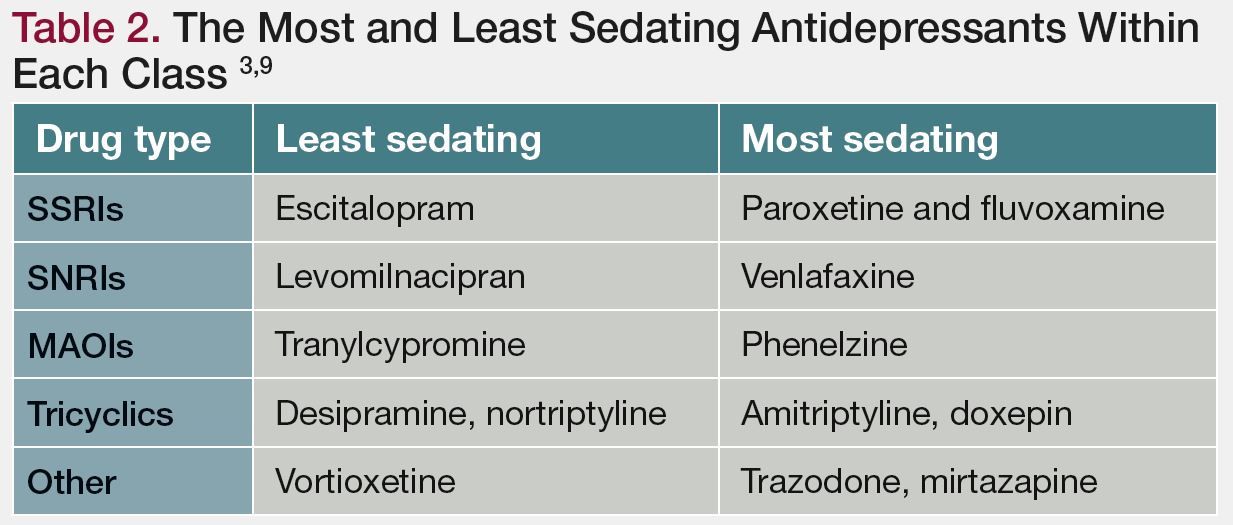

Sedation The Ups And Downs Of A Side Effect

Sedation The Ups And Downs Of A Side Effect

Sedation The Ups And Downs Of A Side Effect